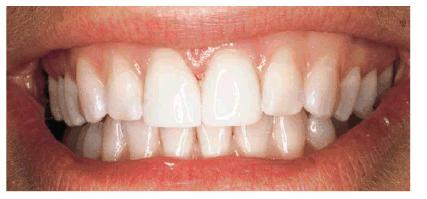

Figur 323s1823d e 18-3E and F: Three porcelain laminates were placed on the central incisors and right lateral. The new laminates also achieved the objective to eliminate the incisal translucency.